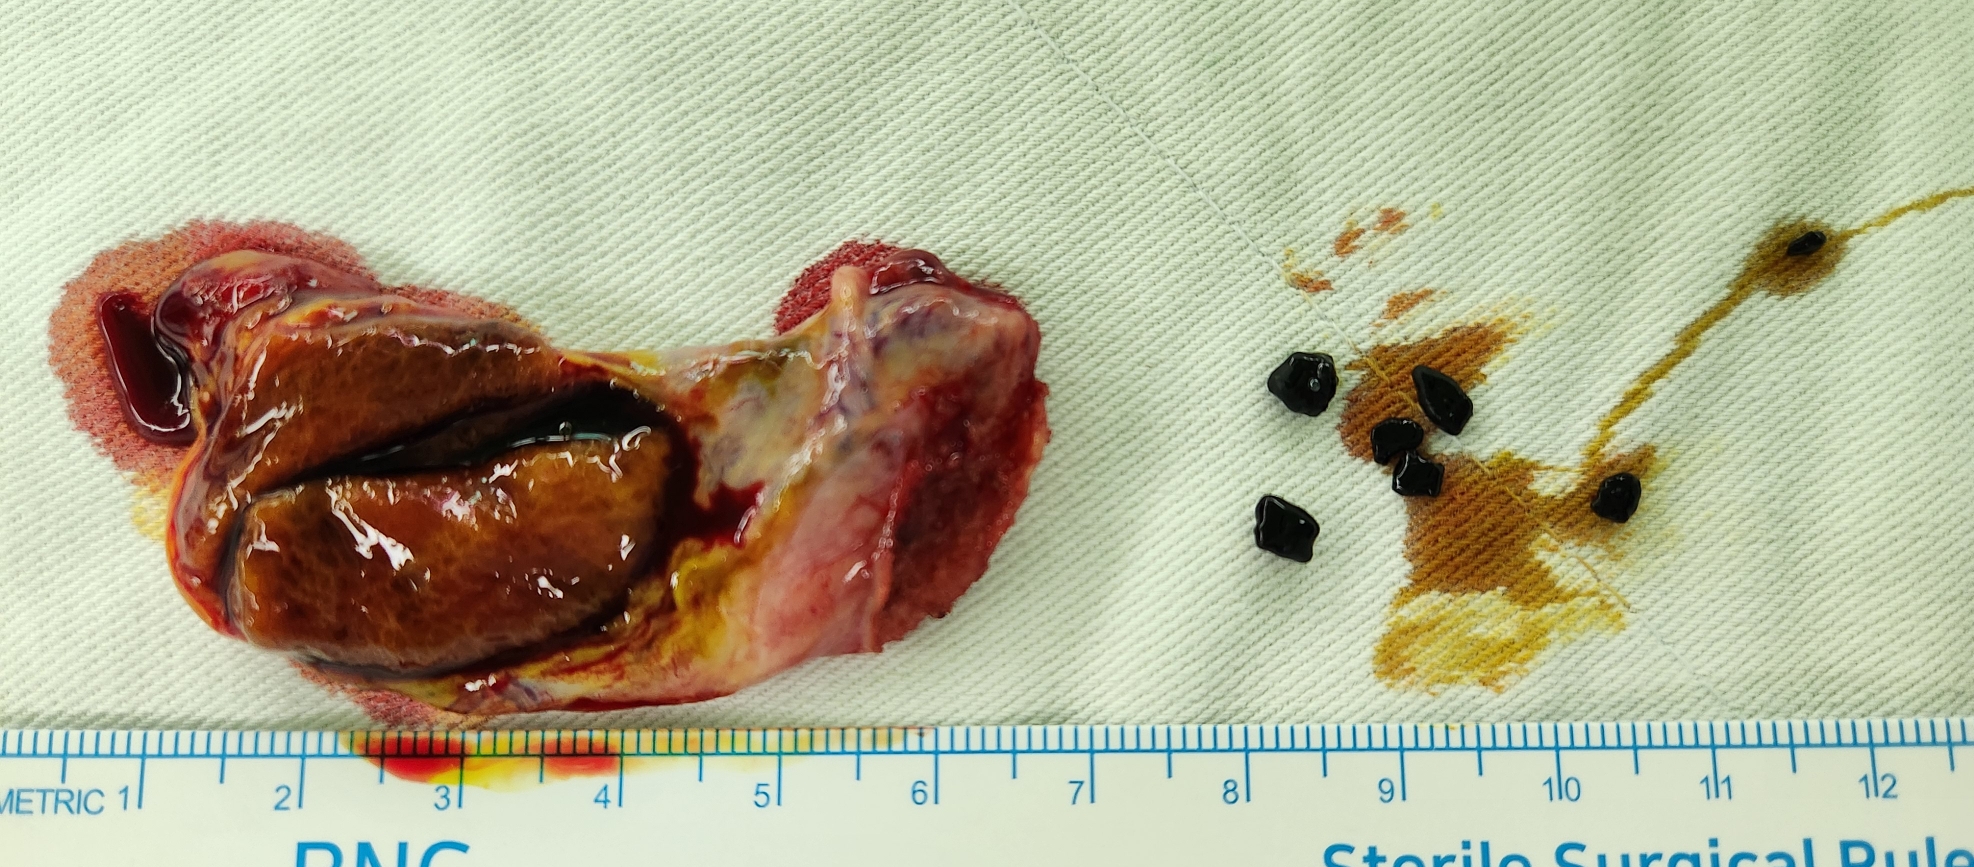

우상복부 복통으로 제 외래로 오셔서 복부 CT시행후 담석으로 수술 위해 제 외래로 오셨던 분입니다.

방금 단일공 복강경 담낭절제술을 시행했습니다.

수술은 20분 걸렸습니다.